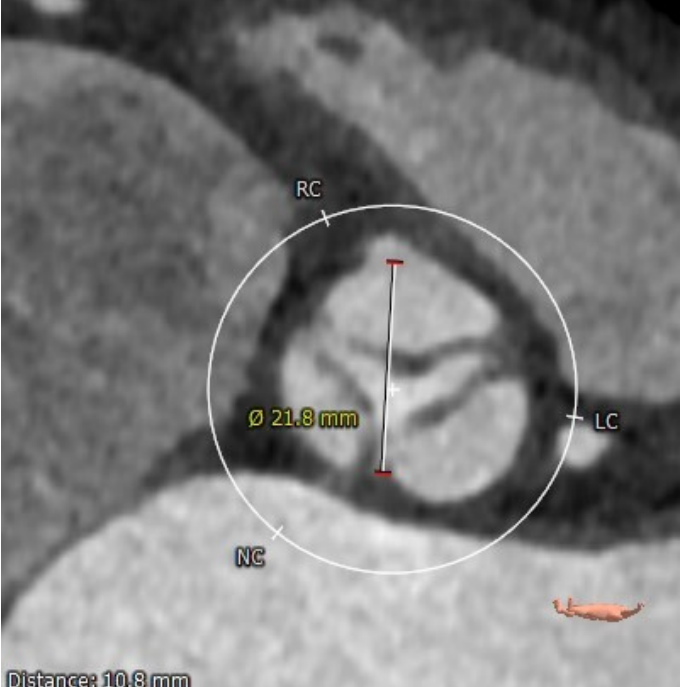

术前CT分析

瓣环

周长:68.1mm 平均直径:21.7mm

法氏窦

直径:25.3*24.2*25.1mm

窦管结合部

平均直径:25.8mm

升主动脉

平均直径:31.9mm

左冠高度高度:14.6mm

右冠高度高度:9.8mm

主动脉瓣角度 44°

钙化积分68mm³